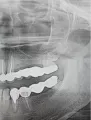

Зуб мудрости под десной растёт в сторону соседнего зуба и уже упирается в него. Соседний зуб находится под коронкой (живой) и на нем держится мост. Боль при накусывании на зуб под коронкой, которая потом моментально проходит.

Один хирург говорит, что сначала надо снимать мост и смотреть можно ли вылечить зуб, который даёт боль. Другой хирург советует сначала удалить зуб мудрости, что возможно он даёт эту боль, но при удалении можно повредить соседний под коронкой.